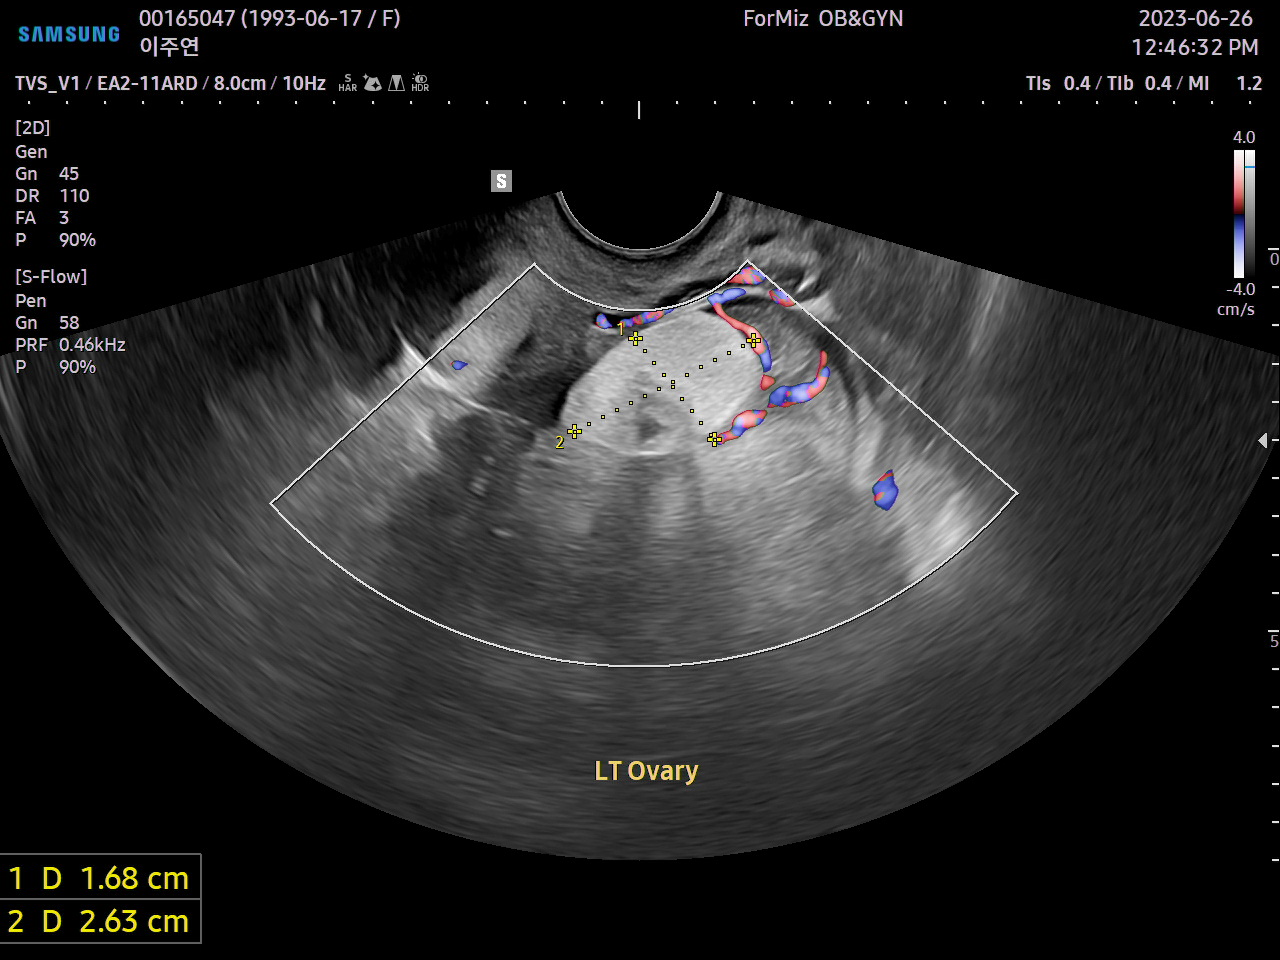

이주연은 사회적 고립, 노동 불안정, 기술 발전, 산업 독성학과 몸 정치학 등을 포괄한 광범위한 리서치와 인터뷰를 바탕으로, 분석적이면서도 시적인 논픽션 무빙 이미지를 연출한다.

Jooyeon Lee works with analytical yet poetic non-fiction moving image with expansive research and interviews to capture urban alienation, labour precarity, technological progress, industrial toxicology and body politics.